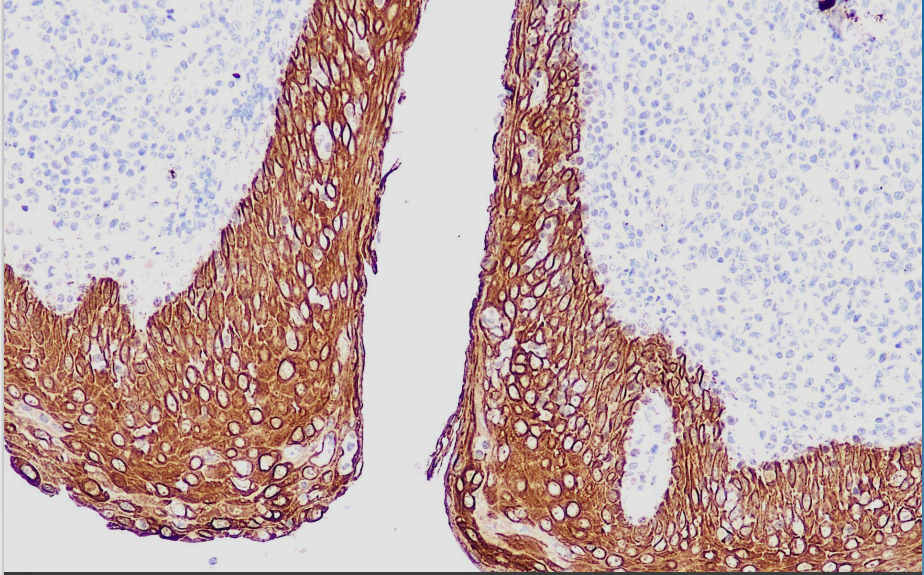

Positive control: tonsils

Cytokeratin HMW AE3 is a high molecular weight keratin antibody that recognizes all basic keratins and marks most epithelial and epithelial-derived tumors.

The high molecular weight cytokeratin antibody reagent specifically binds to the high molecular weight cytokeratin molecular antigen. The immunohistochemistry kit containing the high molecular weight cytokeratin antibody reagent is suitable for the auxiliary diagnosis of certain epithelial tumors.